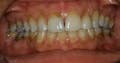

Example: If you were discussing cavities, broken down fillings, or any cosmetic procedure, I would print the image. (Images 1.3, 1.4, far and middle left) You should probably even print a smile or retracted smile photo since you discussed cosmetics. (Go with the more drastic photo that best shows the devastation to the teeth.) (Image 1.5, near left) It is also advantageous to use a black marker to draw arrows next to the teeth being discussed and write some key points to remember, such as crowded, discolored, worn, or broken down. Other supportive ideas behind digital photography include communication with your lab, emails to your specialist, and digital record keeping. (Photos of a current condition and on-going changes)

You may be thinking of all the other ways digital photography can be of value. Once your treatment numbers rise, your dental schedule stats fill up, and procedures are completed, you will want to explore other avenues that can be created by this small investment of a digital camera. Regarding sharing photos, it is a nice finishing touch to share the before and after images with your patients. Never miss an opportunity to print images for patients to take home and share with family and friends. These pre- and post-treatment photos remind them of their previous conditions and how you took care of them. The message is clear — “We deliver on our work, and you can trust us.” (Images 1.6, 1.7, left)